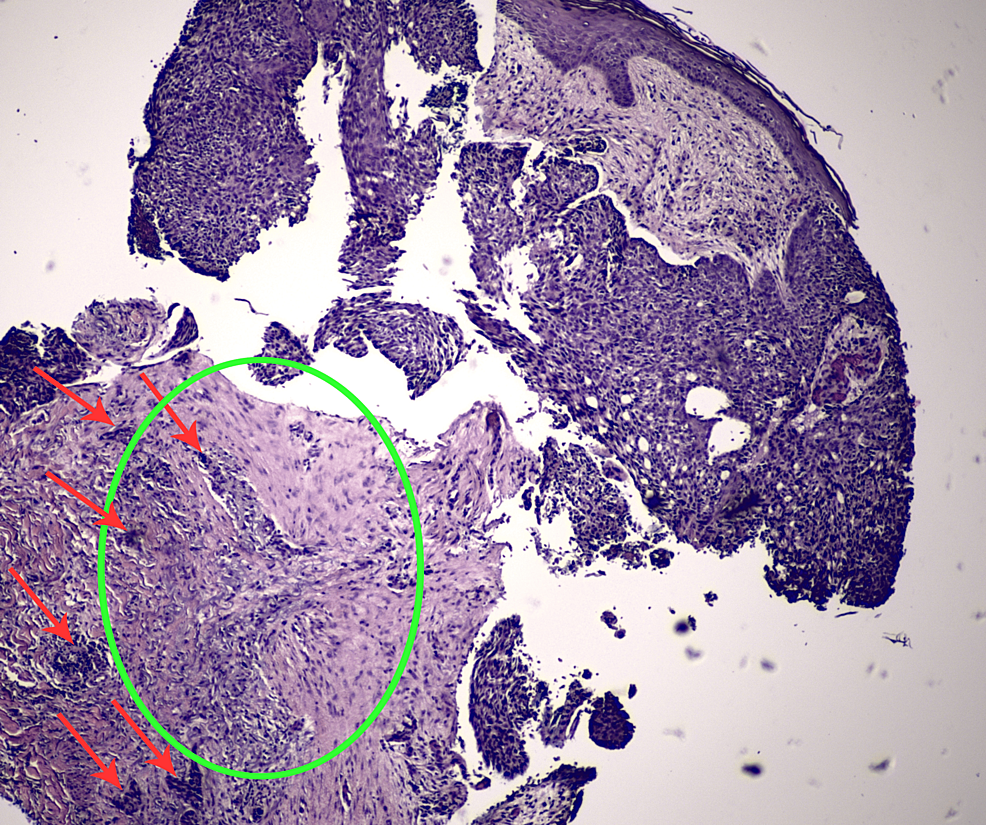

H&E stain of left lateral neck punch biopsy at 10x magnification H&E Punch Biopsy Bcc Your doctor uses a special instrument to take a punch biopsy. Punch biopsy is the preferred method of sampling for most inflammatory dermatoses because it allows the pathologist. Basal cell carcinoma (bcc) is the most common type of cancer in the world. The recommended biopsy techniques for bcc are punch biopsy, shave biopsy, and excisional biopsy. Occasionally a small punch. Punch Biopsy Bcc.